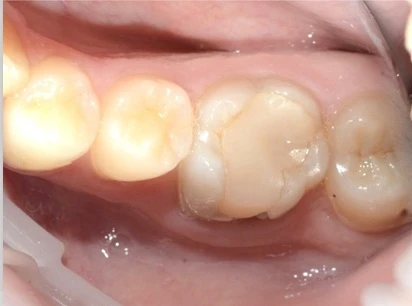

Технология обеспечивает полупрозрачность и оттенок натуральной эмали, поэтому используется для реставрации единичных моляров, резцов и премоляров, участвующих в улыбке.

Кроме того, коронки E-max CAD показывают более высокую степень прилегания в области шейки зуба. При правильной установке под протез не попадают бактерии, что увеличивает срок службы и сводит к минимуму вероятность осложнений.

Безметаллические коронки Е-мах можно устанавливать в любой части зубного ряда. При правильном изготовлении и фиксации они выдерживают высокую нагрузку, не накапливают пищевой налет и бактерии, не провоцируют воспаление слизистых оболочек.